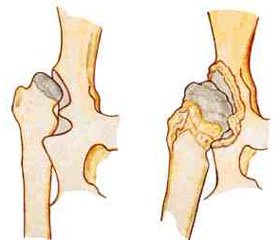

Дисплазия — это общее название нарушений развития и роста органов и тканей, независимо от времени и причины их возникновения. Наиболее частыми дисплазиями у детей раннего возраста являются костные, из которых дисплазия тазобедренного сустава (ДТС) составляет до 15 % в структуре ортопедической патологии, приводящей к статико-динамическим нарушениям и ранней инвалидизации [2].

По данным литературы, до первой половины прошлого столетия учитывали только тяжелую форму дисплазии, а именно врожденный вывих бедра [3]. В те годы легкие формы дисплазии не лечили. С 1970–90-х гг. применяют термин «дисплазия развития», понимая под этим не только вывих, но и предвывих и подвывих тазобедренного сустава. Цифры заболеваемости с прошлого века увеличились десятикратно.

Самыми частыми клиническими симптомами врожденных дисплазий тазобедренного сустава являются: асимметрия кожных складок, укорочение бедра, симптом соскальзывания Маркса — Ортолани и его модификация по Барлоу, ограничение отведения бедра, однако эти данные не патогномоничны, так как, к примеру, асимметрия кожных складок встречается до 30 % в норме [12, 36].

Особенностям строения диспластического тазобедренного сустава посвящено множество работ [12, 40]. Несмотря на достигнутые успехи в диагностике и лечении врожденной патологии тазобедренного сустава и массу предложенных методов консервативного и хирургического лечения, недостаточно изучена динамика развития костной ткани при дисплазии тазобедренного сустава, особенно по рентгенологическим данным.

Необходимость анализа большого количества показателей объясняется разнообразием вариантов нарушения анатомического строения и развития сустава, наблюдаемых при врожденном вывихе бедра. Эффективная оперативная коррекция нарушения строения диспластического тазобедренного сустава может быть осуществлена только при учете всех особенностей его анатомо-функционального состояния [2, 40].